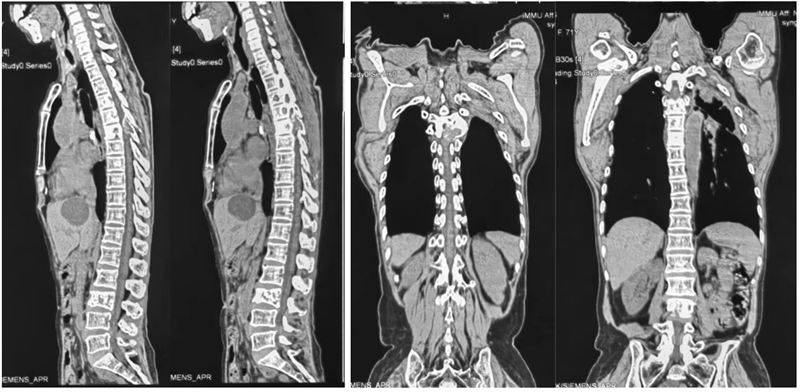

图1a 女,71岁。左肺腺癌靶向药物治疗5年。肺癌脊柱转移(T4-6,L3)。CT矢状位重建示T4-6、L3椎体及T6左侧椎弓根溶骨破坏